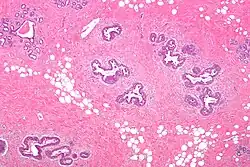

Early histological features expected to be seen on examination of gynecomastic tissue attained by fine-needle aspiration biopsy include the following: proliferation and lengthening of the ducts, an increase in connective tissue, an increase in inflammation, and swelling surrounding the ducts, and an increase in fibroblasts in the connective tissue.[26] Chronic gynecomastia may show different histological features such as increased connective tissue fibrosis, an increase in the number of ducts, less inflammation than in the acute stage of gynecomastia, increased subareolar fat, and hyalinization of the stroma.[24][26] When surgery is performed, the gland is routinely sent to the lab to confirm the presence of gynecomastia and to check for tumors under a microscope. The utility of pathologic examination of breast tissue removed from male adolescent gynecomastia patients has recently been questioned due to the rarity of breast cancer in this population.[57]